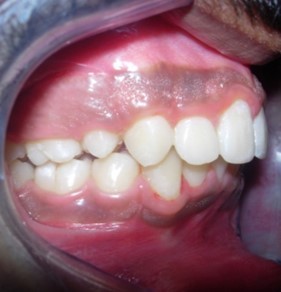

Intraoral assessment. (Figure 1d,Figure 1e,Figure 1f,Figure 1g,Figure 1h).

Figure 1e.Pre-treatment intra-oral-Right

Pre-treatment intra-oral-Right

Figure 1f.Pre-treatment intra-oral-Left

Pre-treatment intra-oral-Left

The maxillary arch was V-shaped with severely proclined and rotated maxillary incisors with a palatally placed 12. The mandibular arch was U-shaped with severe crowding of mandibular incisors, with 43 partially erupted and buccally placed with transpositioned 42 and 43, with 42 mesiolingually rotated, 33 distolingually rotated and 34 distolingually rotated and buccally placed.

Severe increase in overjet and deep bite were both observed. The maxillary midline coincided with the skeletal midline but the mandibular midline was shifted to the right side by 1 mm. Bilateral maxillary posterior crossbite was also observed. On right side the molar relation was Class I and on the left side it was Class II. The canine relation was Class II on the left side and the curve of Spee was increased.